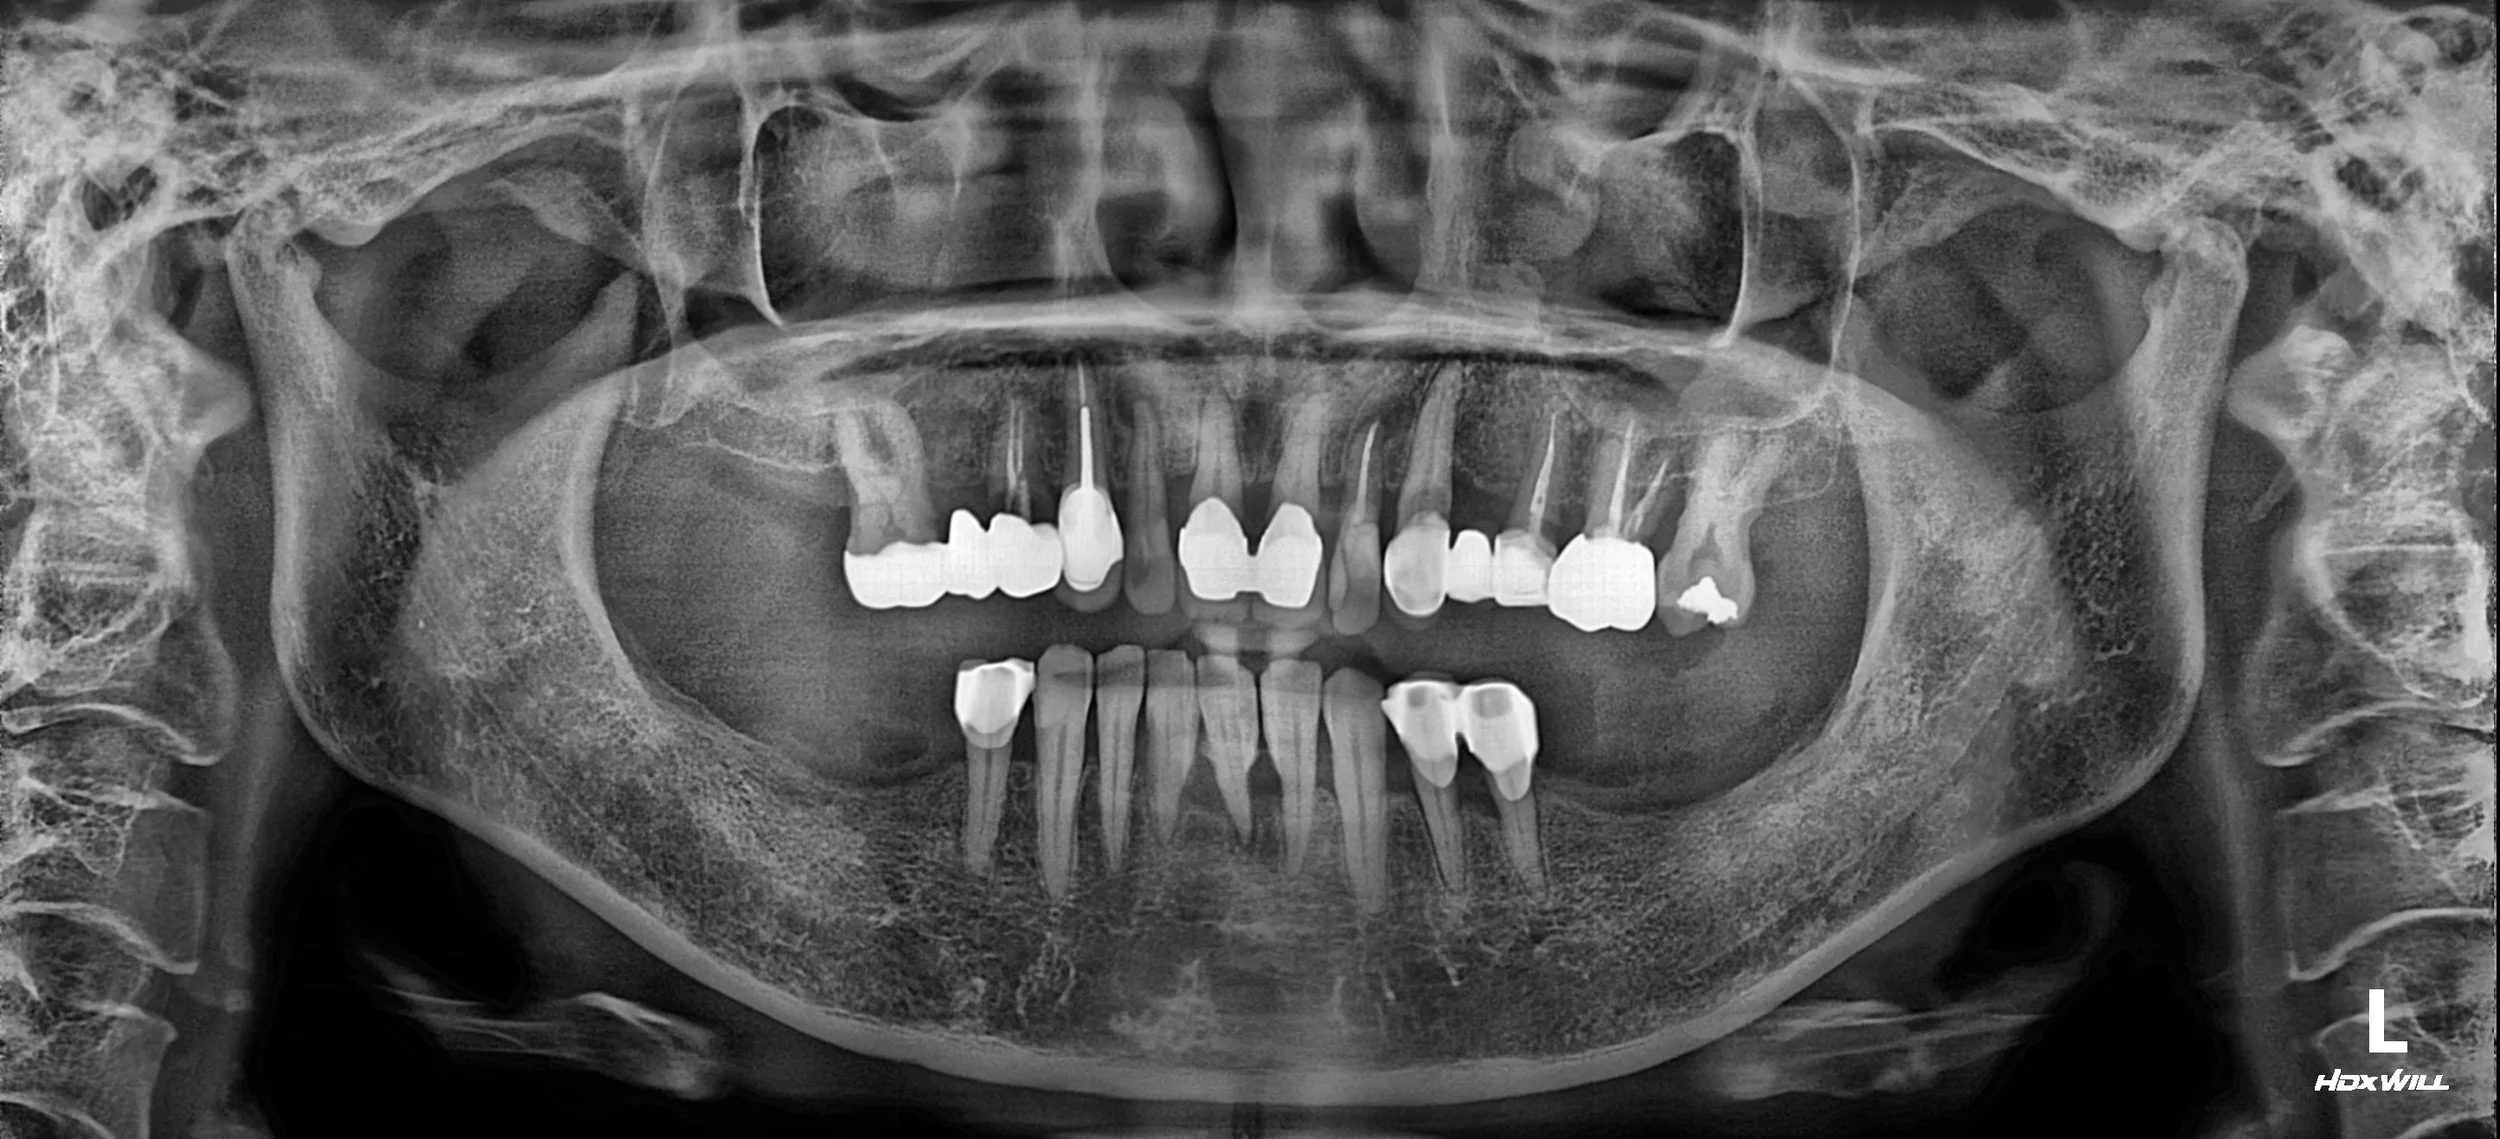

OPG - BEFORE

A female patient in her 50s presented with a severely compromised dentition and significant functional distress. Having relied on ill-fitting partial dentures for a long period, the lack of stable posterior support had led to:

• Occlusal Collapse: Loss of posterior bite force and a resulting decrease in Vertical Dimension of Occlusion (VDO).

• Advanced Periodontal Disease: Severe horizontal and vertical bone loss across both arches, with significant tooth mobility.

• Prosthetic Failure: The existing removable and fixed prosthetics were no longer functional, exacerbating alveolar bone resorption.

1. Periodontal & Surgical Phase: Removal of non-restorable teeth followed by comprehensive periodontal therapy. Dental implants were strategically placed in both the anterior and posterior segments. Extensive guided bone regeneration (GBR) was required in areas of severe atrophy to ensure a stable foundation.